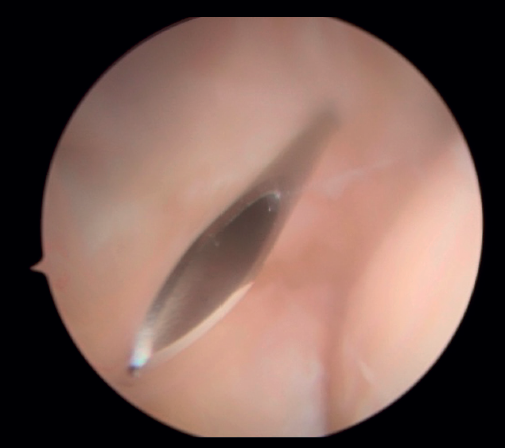

En primer lugar, se realiza el portal anteromedial de visión, incidiendo únicamente la piel y realizando disección roma con un mosquito recto. A continuación, se introduce la vaina del artroscopio, atravesando de forma anterior y proximal el septo fibromuscular medial, en dirección a la cabeza del radio, de forma posterior y distal, para evitar lesionar el nervio cubital y el paquete vascular anterior del codo. Una vez introducida la óptica en el portal medial, se procede a realizar el portal lateral proximal como portal de trabajo. Se realiza bajo visión directa, utilizando como guía una aguja intramuscular de fuera a dentro, para localizar el punto de entrada que permita mejor ángulo de trabajo (Figura 4). Posteriormente, se incide en la piel y se realiza disección roma con un mosquito recto para entrar en la articulación (Figura 5).

Figura 5. Realización del portal lateral (paciente en decúbito lateral, codo derecho, visión desde el portal medial).